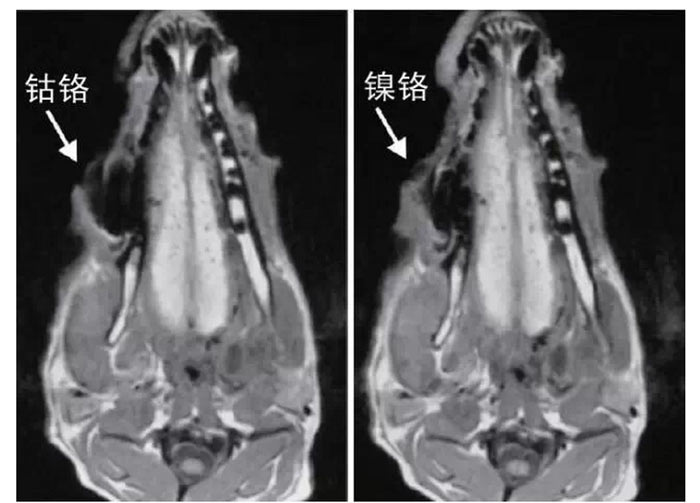

文獻(xiàn)研究中常使用的金屬包括鎳鉻合金、鈷鉻合金、低鈦合金、純鈦、金合金、金鈀合金、銀鈀合金等成分如表所示。大量研究得出近乎一致性的結(jié)論。金合金、金鈀合金、銀鈀合金對(duì)MRI影響甚微,與全瓷材料、丙烯酸樹(shù)脂極為相似,表現(xiàn)為修復(fù)體影像邊緣光滑、無(wú)變形、無(wú)偽影;純鈦金屬對(duì)MRI影響較小,接近于全瓷材料;但有的研究卻發(fā)現(xiàn)純鈦在核磁共振場(chǎng)中也產(chǎn)生偽影,但偽影涉及的掃描層數(shù)較少;低鈦合金(鈦合金)對(duì)MRI影響較大,介于純鈦和鎳鉻合金之間,中度偽影;鎳鉻合金、鈷鉻合金對(duì)MRI影響很大,鈷鉻合金更甚;表現(xiàn)為重度偽影、圖像扭曲變形(圖1、圖2)。不難看出,對(duì)MRI 影響,全瓷材料、樹(shù)脂材料<金合金等貴金屬<純鈦<低鈦合金<鎳鉻合金<鈷鉻合金。有研究發(fā)現(xiàn)鈷鉻合金橋偽影大小與修復(fù)體長(zhǎng)軸一致,影響范圍為固定橋近遠(yuǎn)中徑2倍,頰舌徑的4倍;相同外形金屬修復(fù)體厚度增加,偽影增加。單個(gè)金屬樁核偽影可波及到上頜竇、牙槽骨、舌體、舌下腺等組織器官,但對(duì)眼底、眼內(nèi)容物、腦組織和頸椎成像基本無(wú)影響。

圖2 4種金屬冠在犬MRI檢查中的影響,圖片引自《實(shí)用口腔醫(yī)學(xué)雜志》2014第30期《4種金屬冠對(duì)磁共振成像影響的對(duì)比研究》一文,作者高嵐等